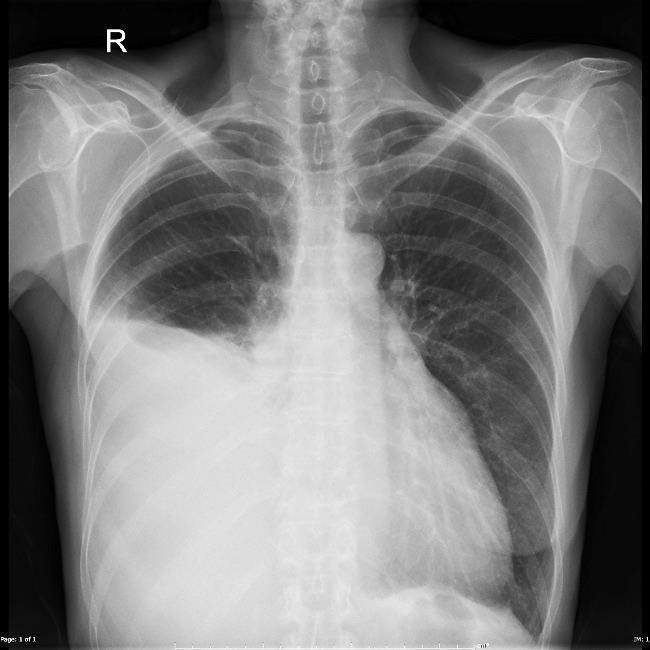

Efusão pleural unilateral volumosa (aspecto radiográfico) e efusão peritoneal (ascite).